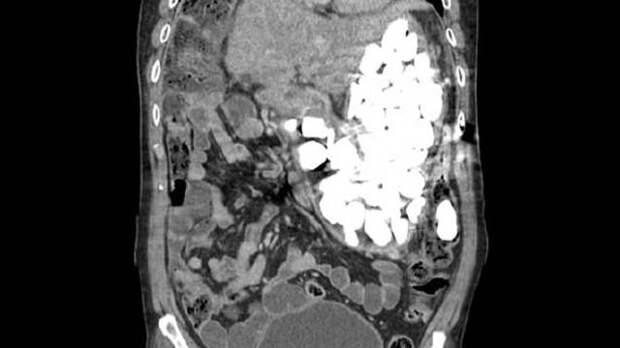

В ходе беседы с врачом пациент признался, что часто глотает камни и монеты, чтобы успокоиться. Рентген показал, что мужчина довольно нервный: весь желудок был заполнен камнями, монетами и бутылочными крышками.

Медикам пришлось проводить операцию для того, чтобы очистить желудок пациента. Общая масса извлеченных оттуда предметов составила около двух килограммов.